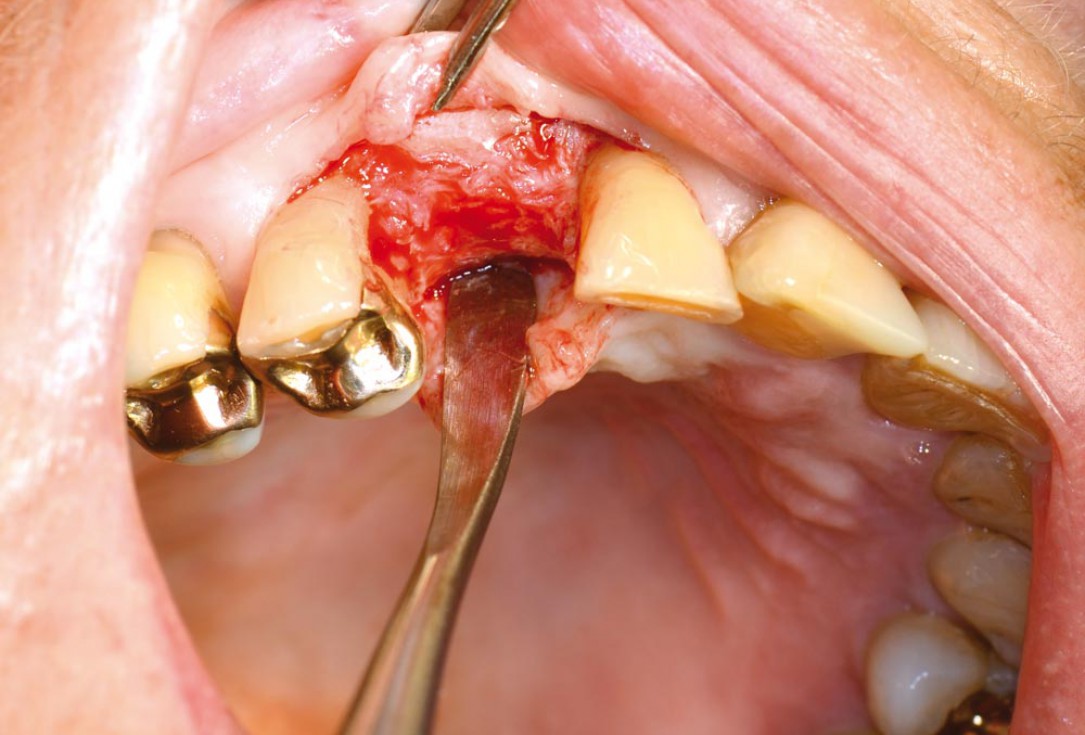

01/12 - Initial situation - bone defect in maxilla after loosing right canine

Block augmentation with maxgraft® in the maxilla - PD Dr. Dr. F. Kloss